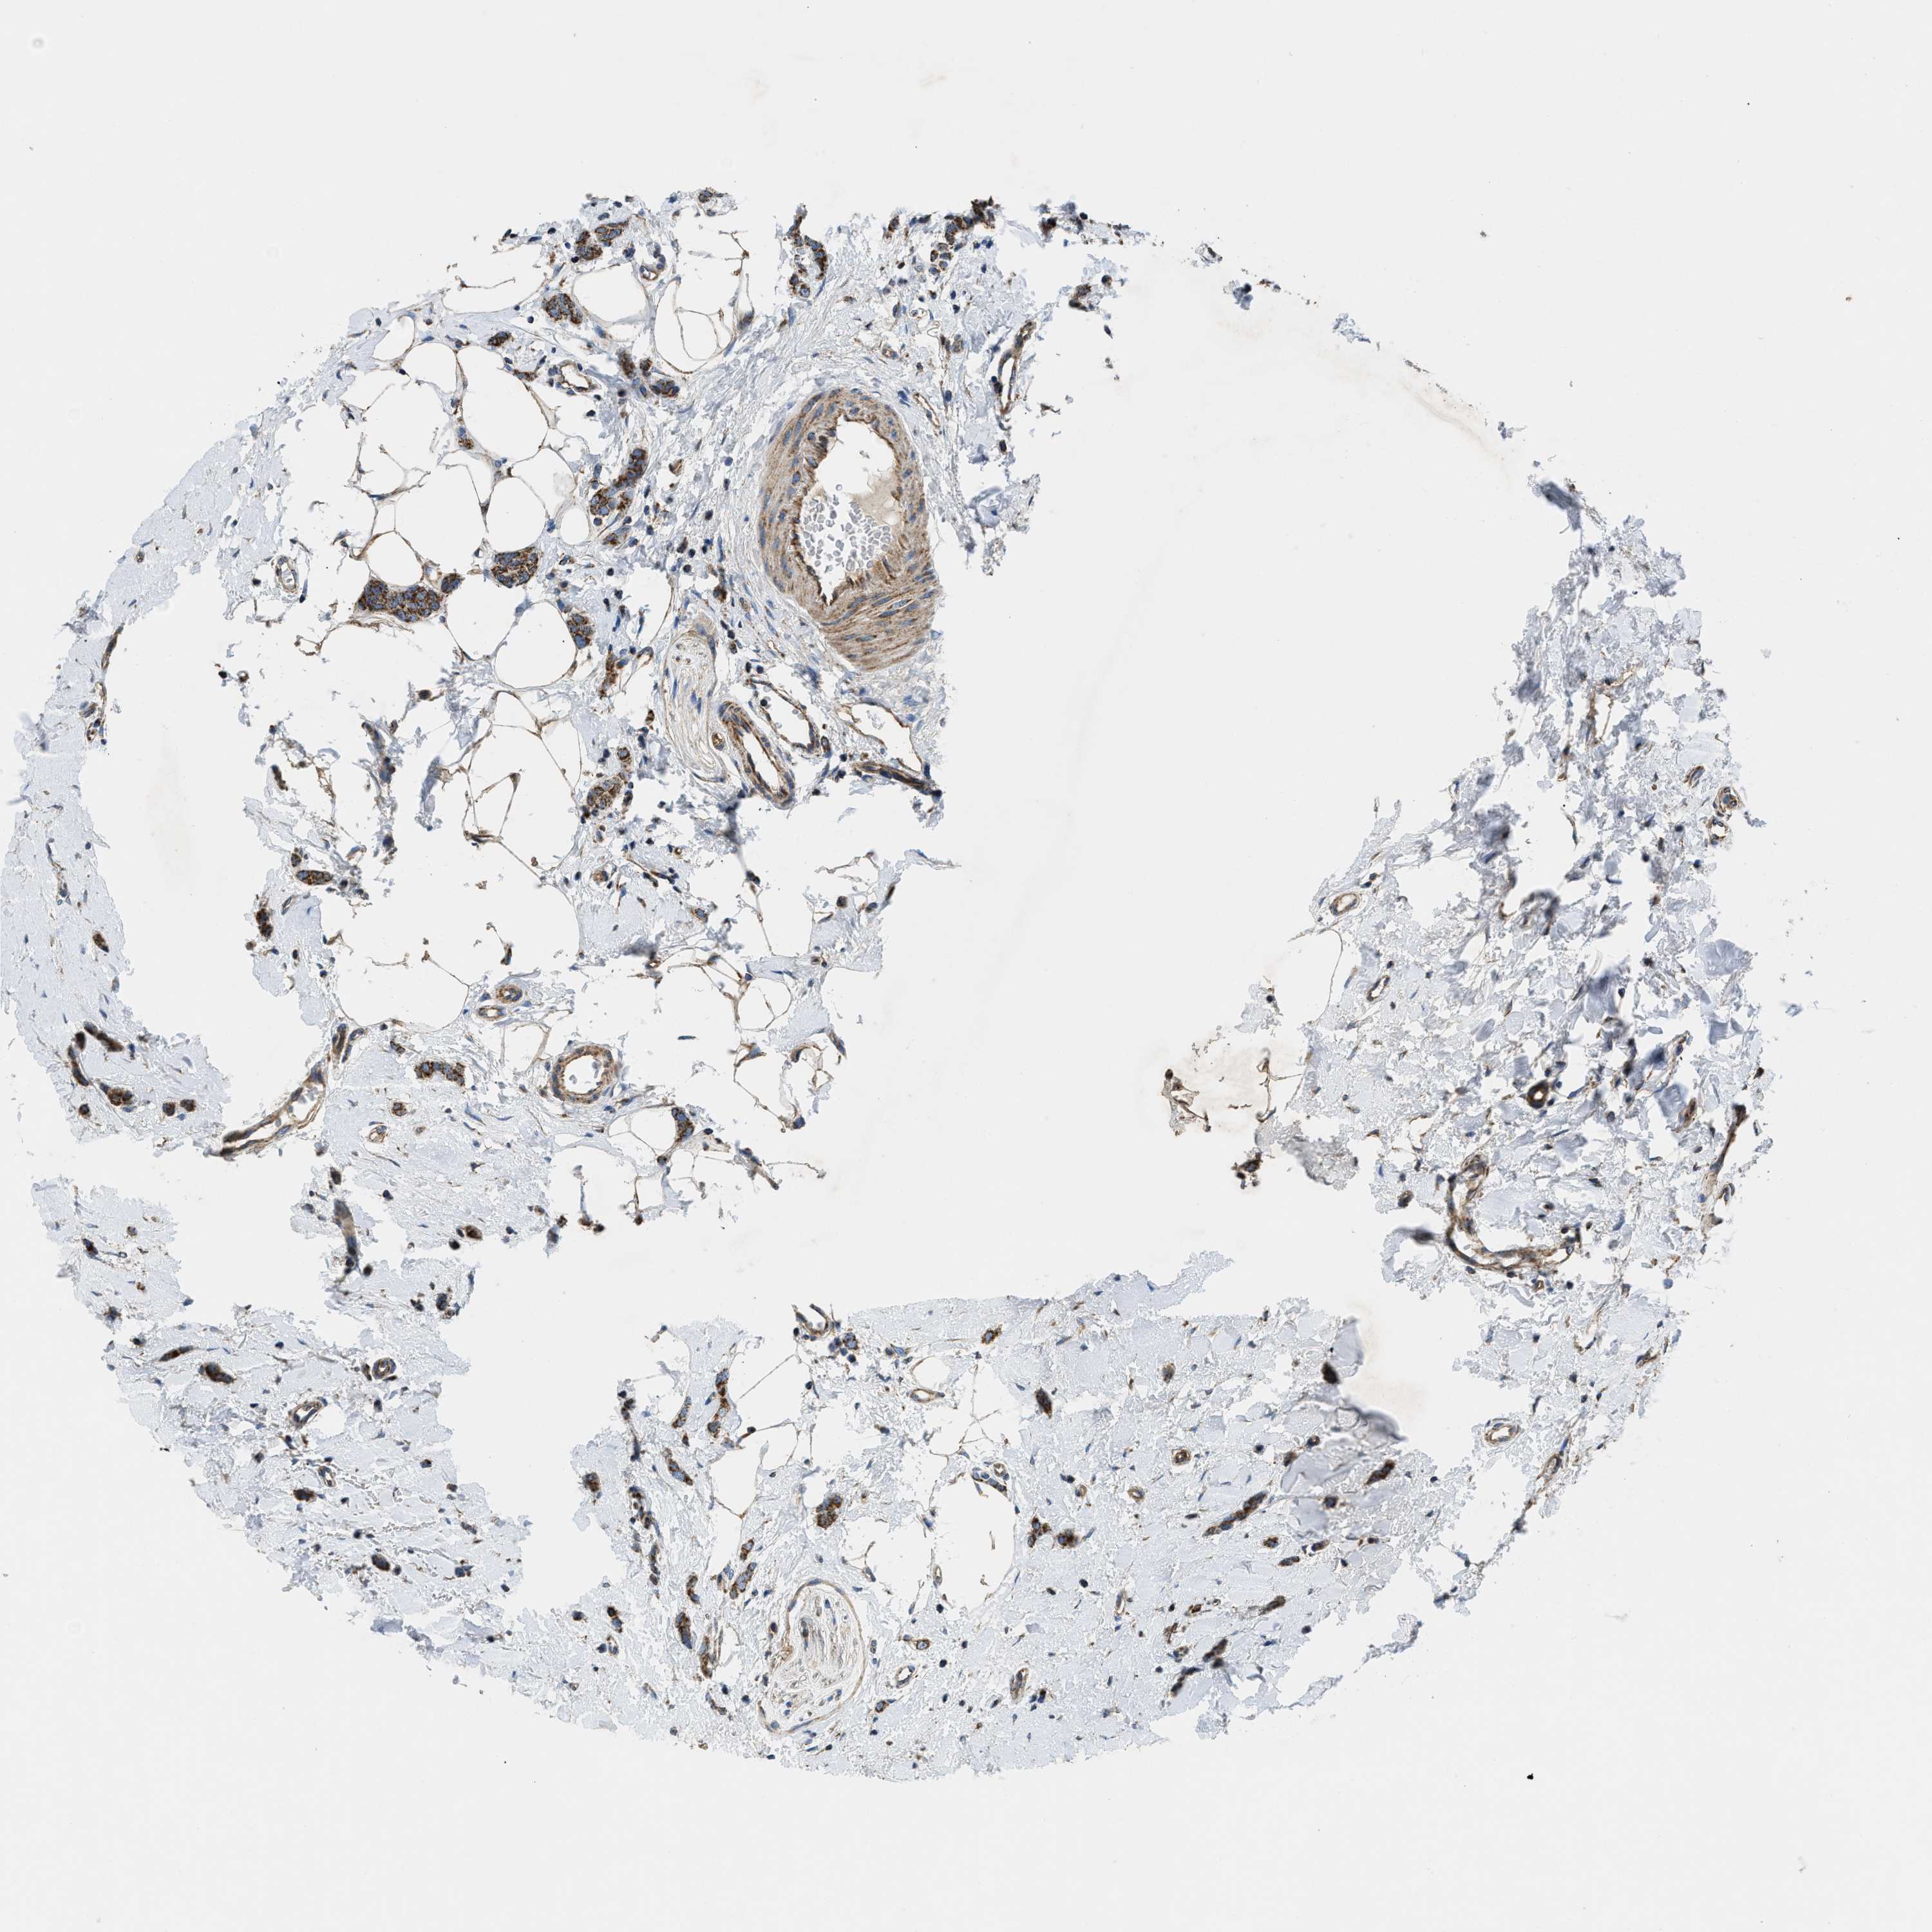

CANCER BREAST CANCER Show tissue menu

BRCA TCGA BRCA VALIDATION PROTEIN EXPRESSION